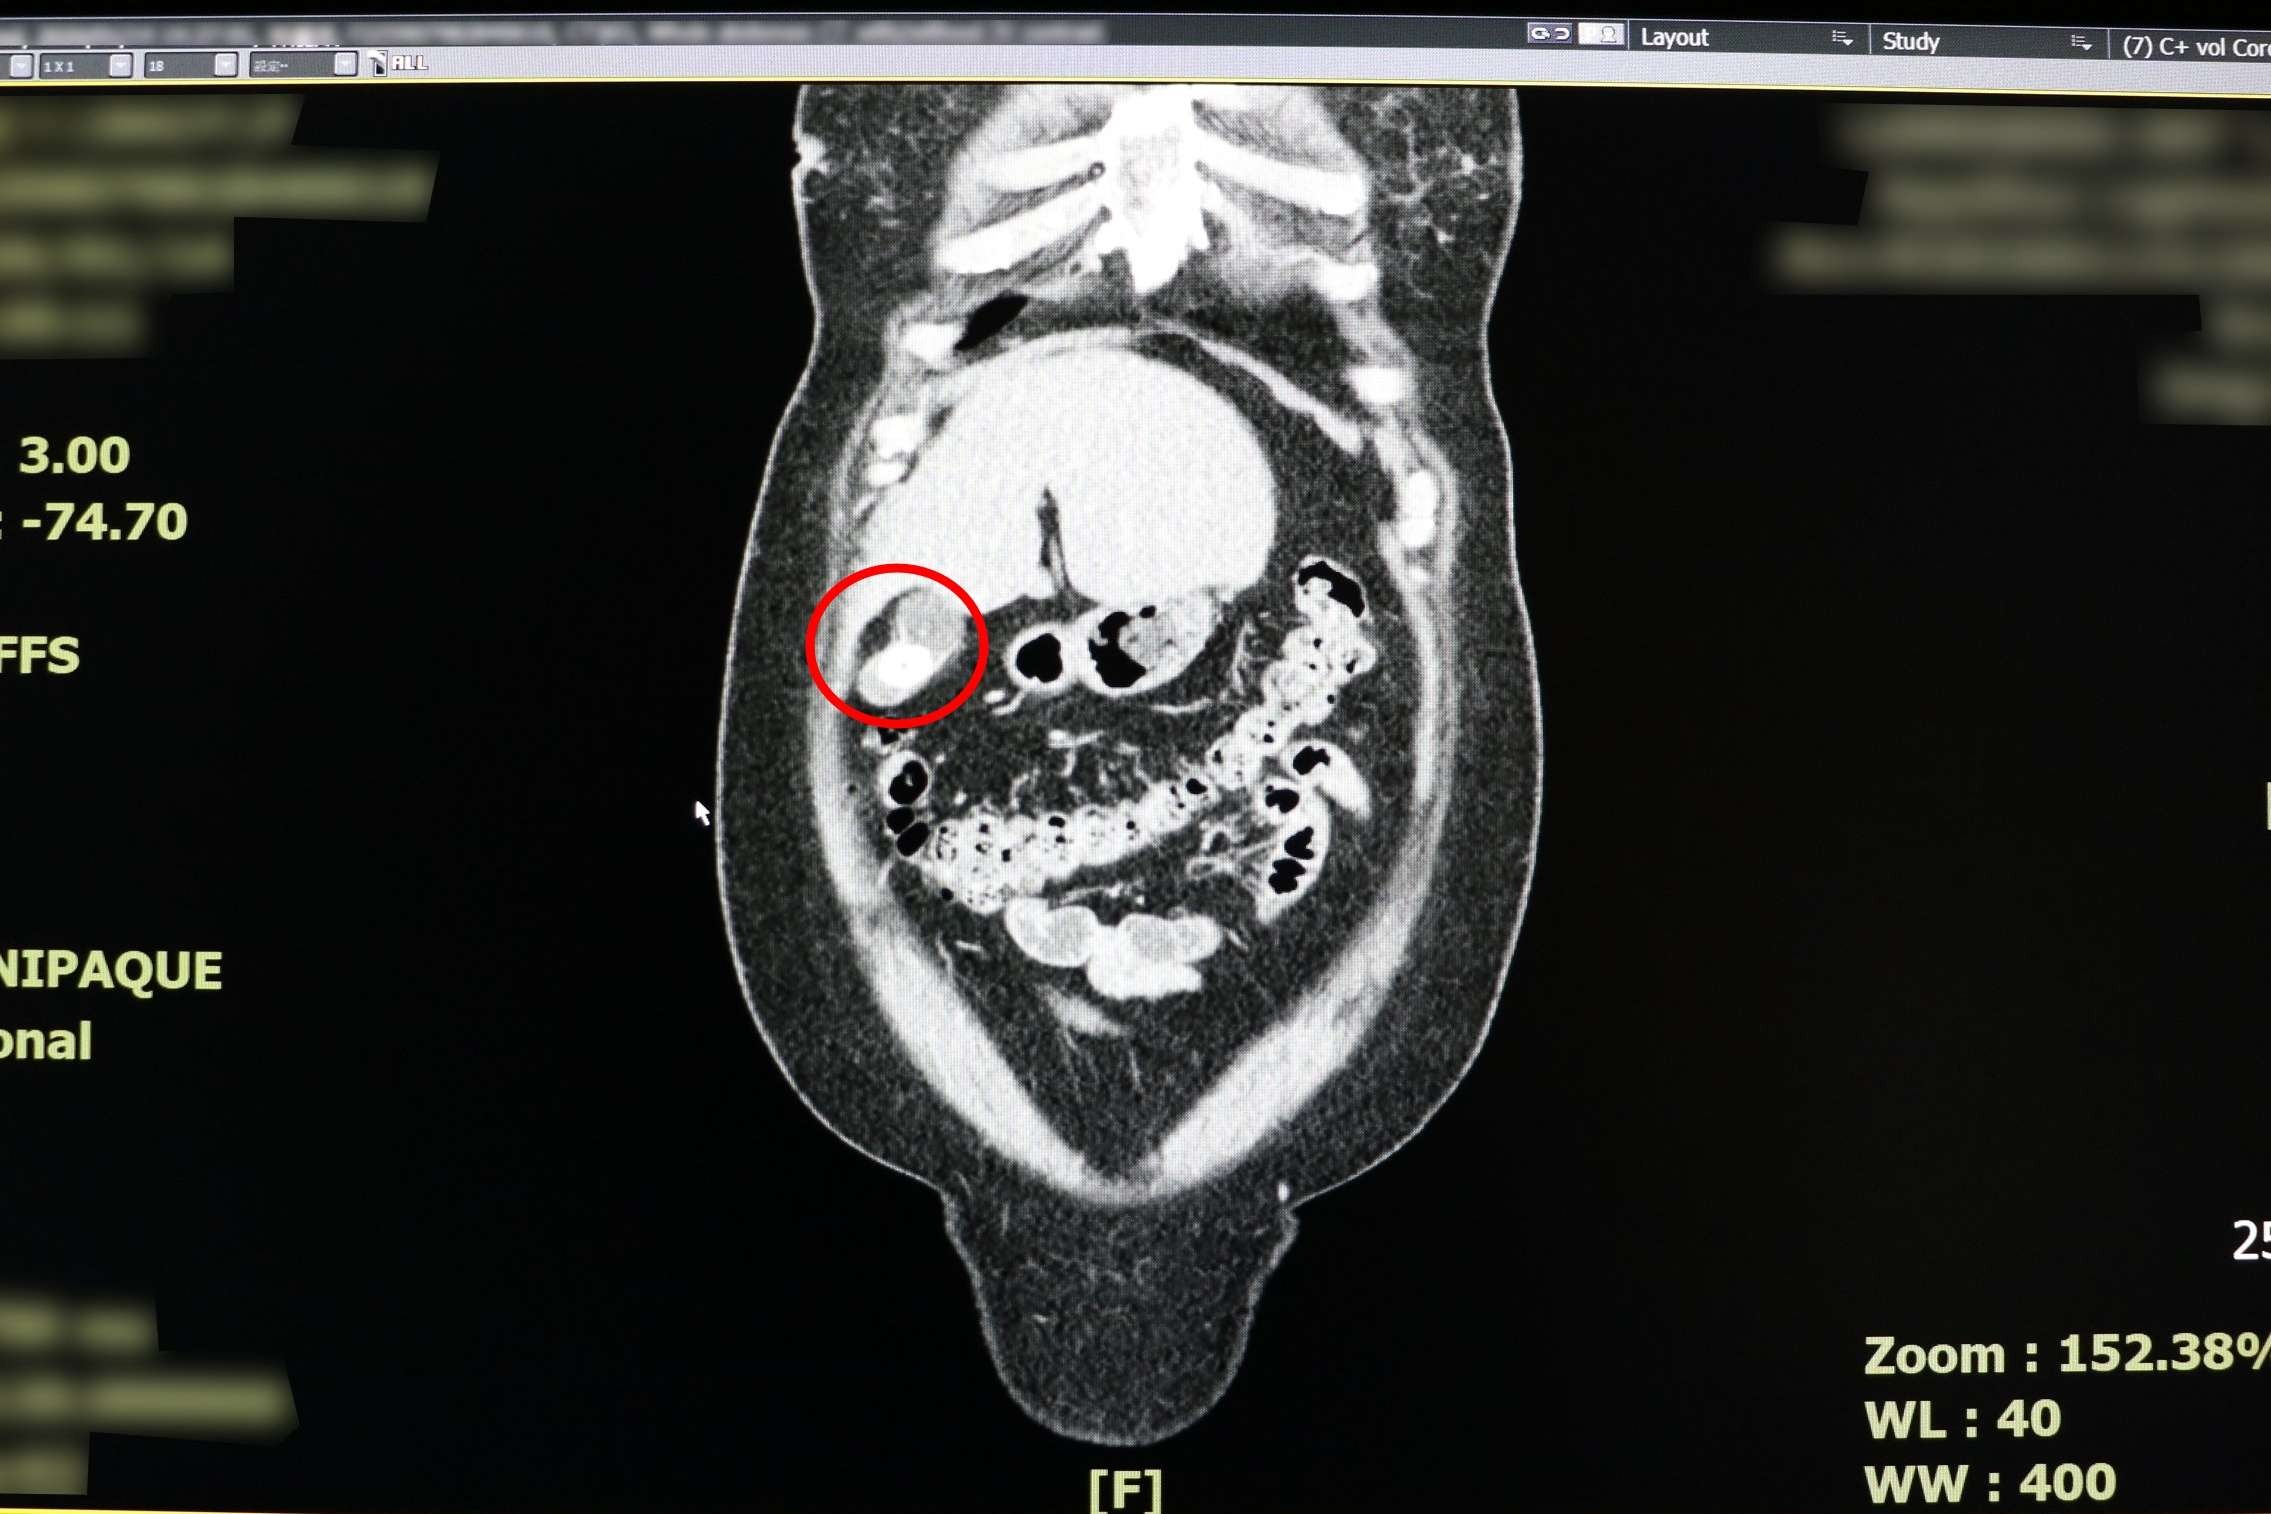

反覆上腹部疼痛時,別再以為只是胃病,當心是「體內未爆彈」膽囊炎作祟。一名38歲女性日前因持續2天劇烈上腹痛,先後到診所與地區醫院就診,皆被診斷為胃炎,服藥與打止痛針仍未改善,求診聯新國際醫院急診室,經醫師朱海慶詢問病史與電腦斷層檢查,會診一般外科醫師張堯任,確診為急性膽囊炎。

根據統計,國人膽結石盛行率超高,平均每10位當中即有1位有膽結石,其中「40歲、女性、肥胖以及曾懷孕」為高風險族群。臨床觀察顯示,30至50歲女性最常見。雖然盛行率超高,但三分之二患者終其一生不會出現症狀,僅少數因結石過大、滾動或堵住膽囊出口引發劇痛才需治療。

張堯任提醒,時下流行的「168斷食法」,不利於膽囊健康,因肝臟在空腹時仍持續製造膽汁,長時間不進食會造成膽汁淤積,隨著水分被吸收後變濃稠,增加結石風險。他將膽結石引發疼痛的病程分為三階段,症狀性膽結石,結石堵塞造成陣發性疼痛,當結石移開,疼痛即緩解;慢性膽囊炎,長期反覆疼痛會導致膽囊壁增厚,形成器官慢性發炎狀態;急性膽囊炎,結石堵塞膽道,膽汁無法排除引發血液循環受阻、化膿、壞死,甚至引發敗血症。